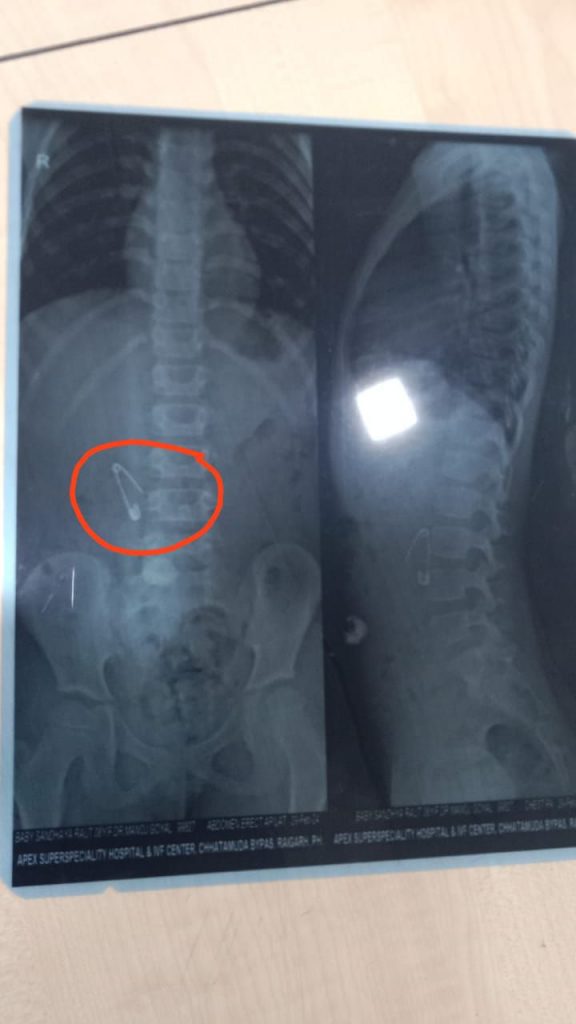

पिता रविशंकर ने बताया कि बालिका के पेट में पिन साफ दिखाई दे रहा हैं. वर्तमान समय में इंडोस्कोप से निकालने का प्रयास की बात कही है.वे यह प्रयोग असफल रहा तो ऑपरेशन के माध्यम से निकाला जायेगा।